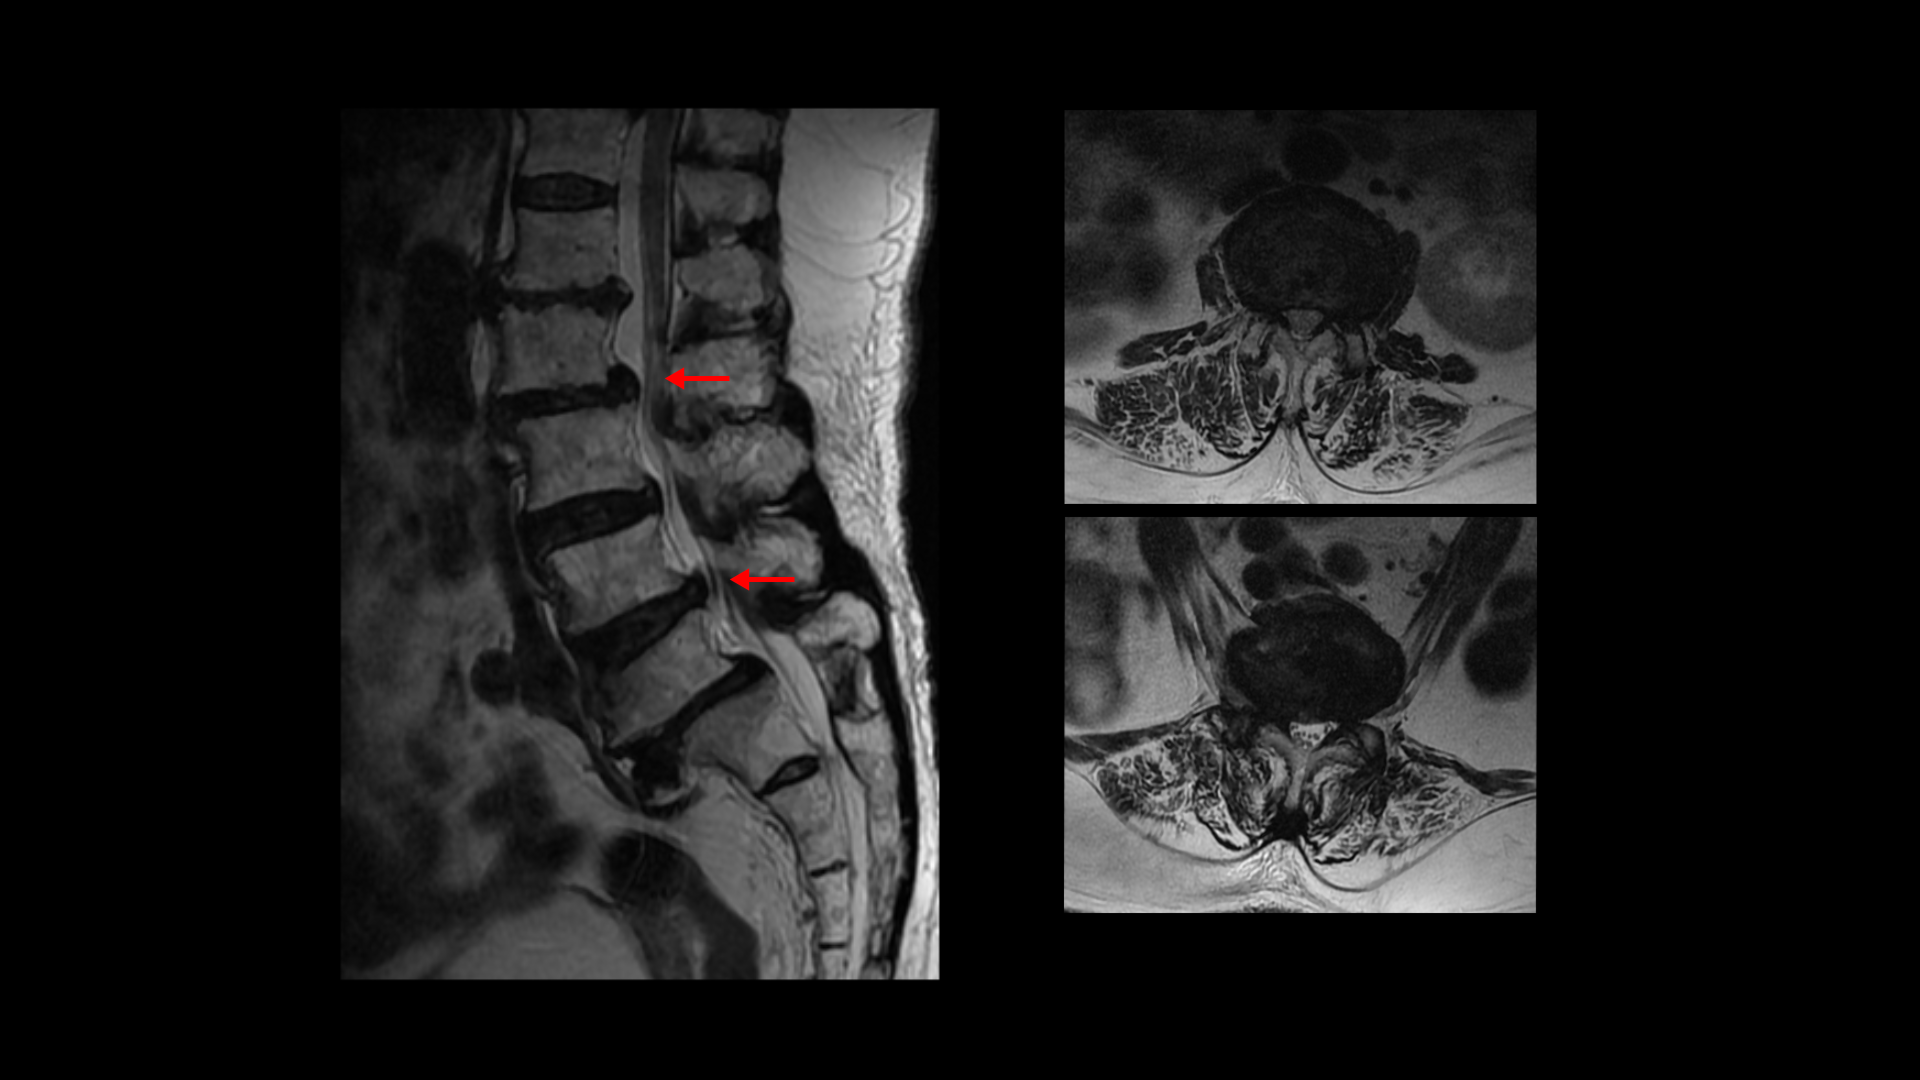

이분 MRI를 보면 보시다시피 허리의 5마디가 전부 퇴행이 진행되어 있습니다.

우선 전방전위가 2마디에 있고

여러 마디 2번 3번, 4번 5번에 척추관협착이 있고

2번 3번, 4번 5번, 오른쪽 신경가지가 빠져나가는 구멍들이 다섯 마디 전부가 다 오른쪽 좁아져 있습니다.

이분의 오른쪽 엉치와 다리가 저리고 아픈 원인은 이것 때문인 걸로 보입니다.

그런데 이분은 허리도 굽으셨는데 척추근육, 특히 허리를 세워주는 기립근을 mri에서 보면 허리 다섯 마디 전체에서 기립근의 근육이 지방으로 변해서 하얗게 보이는 지방화가 심합니다.

이렇게 근육이 지방으로 심하게 변하고 기능이 떨어지면 허리를 펴기가 어렵고 허리가 아플 수 밖에 없습니다. 여기 건강한 기립근과 비교해서 보면 그 차이를 금방 알 수가 있습니다. 기립근 크기도 차이가 크고 하얗게 지방으로 변해버린 부분을 잘 보실 수 있습니다.